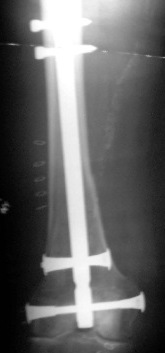

postoperativer Befund nach geschlossener Nagelung